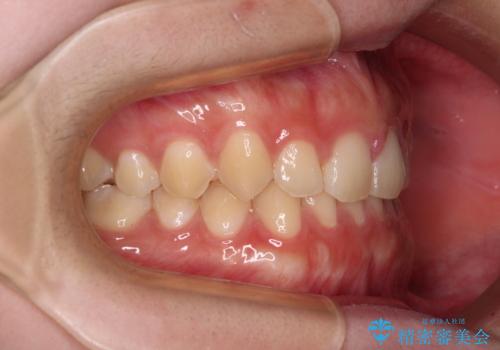

前歯のすきっ歯を治したい インビザラインによる矯正治療

- 上顎前歯の隙間を気にして来院された患者様です。

目立たない装置を希望とのことで、インビザラインを用いて矯正治療を行うこととしました。

一度インビザラインのマウスピースセットをお渡しすると1年以上来院されず、マウスピースを破損したり紛失したりすると来院されるというのんびりとしたペースで治療を行ったため、4年間という長期にわたる治療となりました。

最終的には隙間は全て閉じ、綺麗な仕上がりとなりました。